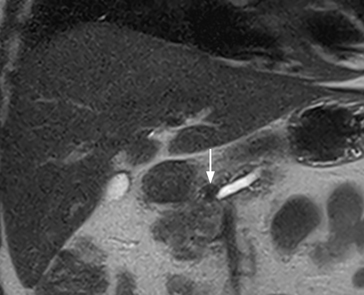

Aspetti RM: piccolo nodulo dell’istmo pancreatico ipointenso in T2.

image